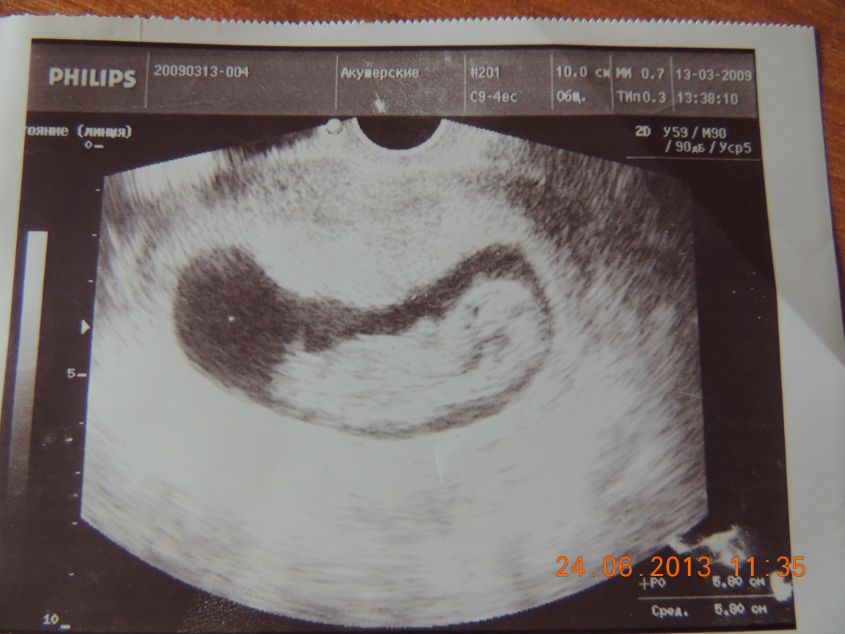

А это Маришка моя на таком же сроке была

Малыши мои сладкие